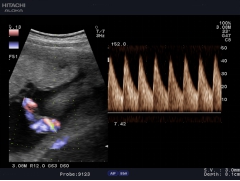

通過復(fù)合陣列探頭及SIP、AIP等多種成像技術(shù),為臨床帶來優(yōu)質(zhì)的二維圖像和敏感的血流,可以更加真實(shí)的反映血管的灌注情況,真實(shí)再現(xiàn)微細(xì)血管解剖形態(tài)。

作為原裝進(jìn)口的全身應(yīng)用型高檔全數(shù)字化彩色多普勒超聲診斷系統(tǒng),它在腹部、泌尿、婦產(chǎn)、乳腺、甲狀腺、淺表、腔內(nèi)、心臟等各個領(lǐng)域都有完美的圖像表現(xiàn)及豐富的應(yīng)用支持。